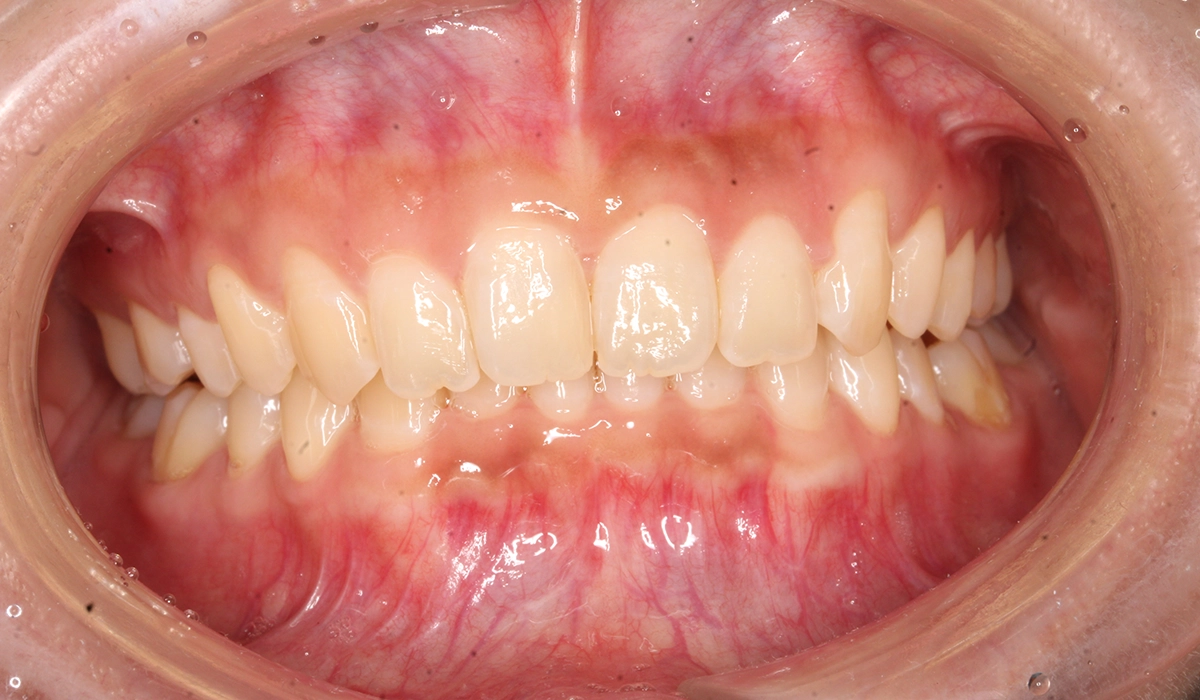

術前:正面

術後:正面